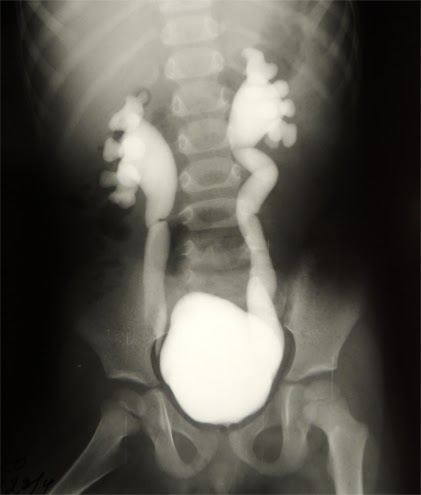

Мегауретер у детей что это

Мегауретер у детей что это 112 фотографий